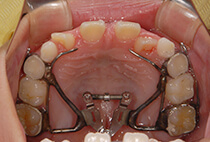

急速拡大装置、上顎前方けん引装置、コルチコトミー

診断の結果は、以下が原因の骨格性反対咬合。

反対咬合でよくあるケースです。

治療方法は、小さな上顎の成長誘導。

急速拡大装置と前方けん引装置を使用します。

かみ合わせもお顔立ちも大きく改善。

その後も機能訓練×かみ合わせの維持をコツコツ継続。

成長のピークに合わせて上顎をもう一度拡大し、前歯のかみ合わせをさらに安定化。

成長期の波に合わせることで、より調和の取れた横顔へ。

治療開始から6年後。

治療終了後2年経っても、安定したかみ合わせと自然な横顔をキープ。

2年生で外科矯正と言われた受け口も、4年生になる頃にはすでに「バランスの良いお顔立ち」に。のびのびと成長期を過ごすことができました。